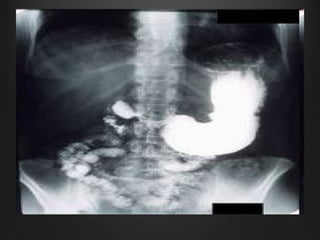

PUD - DiagnosisPUD - Diagnosis

• Niche on the lesser curveNiche on the lesser curve

with notch on the greaterwith notch on the greater

curvaturecurvature

• 58.

• Niche onthe lesser curveNiche on the lesser curve with notch on the greaterwith notch on the greater curvaturecurvature